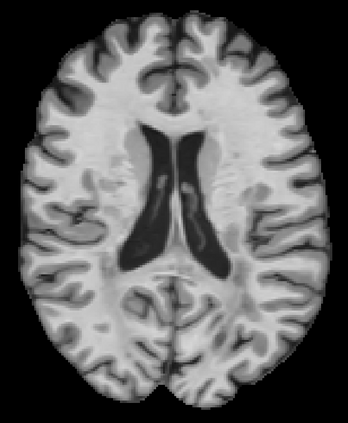

Recently, segmentation methods based on Convolutional Neural Networks (CNNs) showed promising performance in automatic Multiple Sclerosis (MS) lesions segmentation. These techniques have even outperformed human experts in controlled evaluation conditions such as Longitudinal MS Lesion Segmentation Challenge (ISBI Challenge). However state-of-the-art approaches trained to perform well on highly-controlled datasets fail to generalize on clinical data from unseen datasets. Instead of proposing another improvement of the segmentation accuracy, we propose a novel method robust to domain shift and performing well on unseen datasets, called DeepLesionBrain (DLB). This generalization property results from three main contributions. First, DLB is based on a large group of compact 3D CNNs. This spatially distributed strategy ensures a robust prediction despite the risk of generalization failure of some individual networks. Second, DLB includes a new image quality data augmentation to reduce dependency to training data specificity (e.g., acquisition protocol). Finally, to learn a more generalizable representation of MS lesions, we propose a hierarchical specialization learning (HSL). HSL is performed by pre-training a generic network over the whole brain, before using its weights as initialization to locally specialized networks. By this end, DLB learns both generic features extracted at global image level and specific features extracted at local image level. DLB generalization was validated in cross-dataset experiments on MSSEG'16, ISBI challenge, and in-house datasets. During experiments, DLB showed higher segmentation accuracy, better segmentation consistency and greater generalization performance compared to state-of-the-art methods. Therefore, DLB offers a robust framework well-suited for clinical practice.